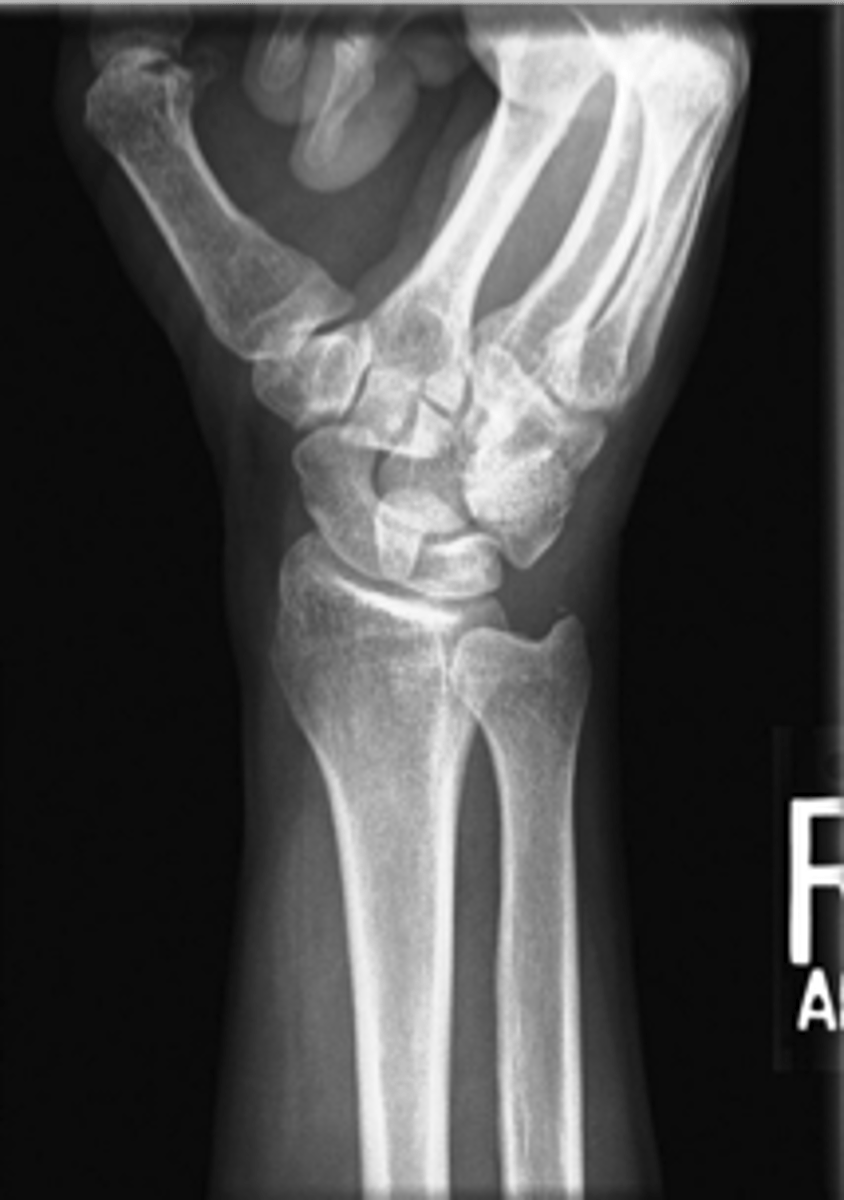

Lateral wrist